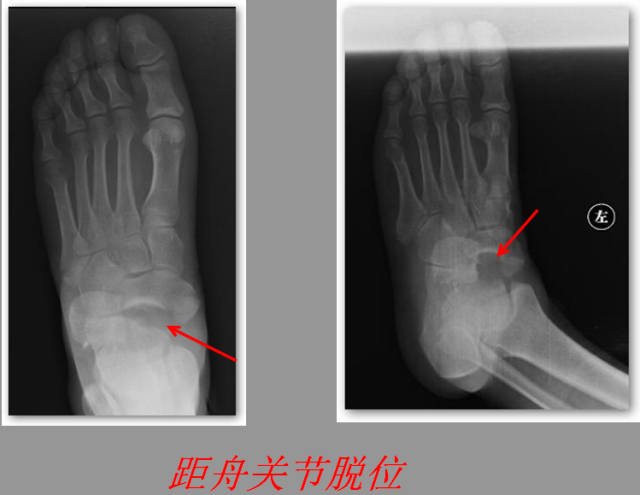

关节脱位篇

02

定义:关节脱位是暴力、关节感染、附近软组织挛缩或先天骨发育障碍造成的关节对位关系部分或完全脱离,即为半脱位或脱位。临床上以创伤性脱位*常见。